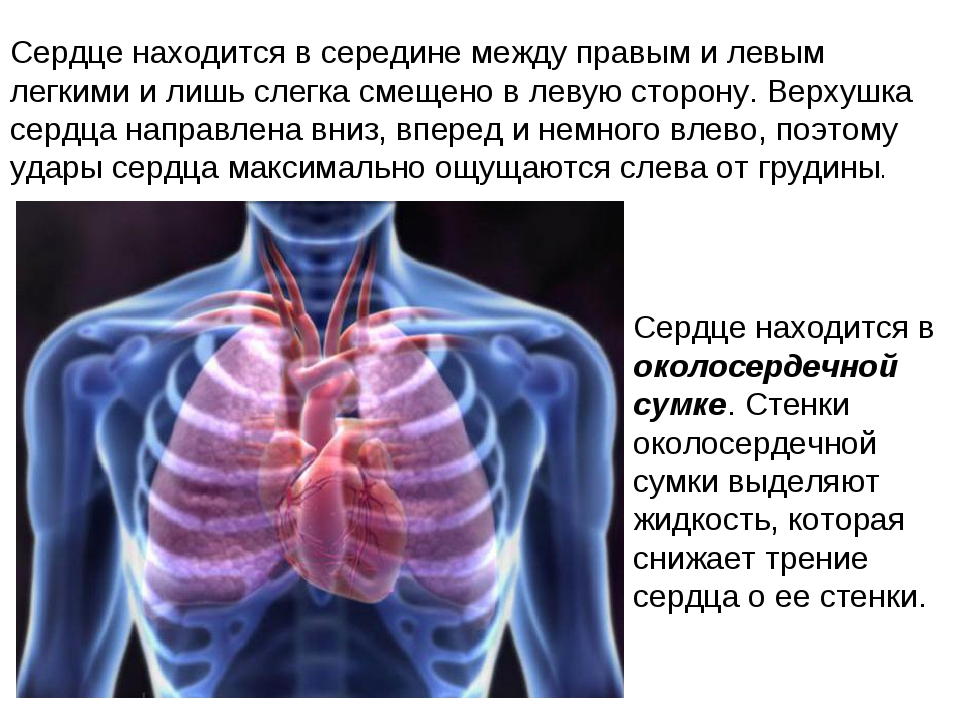

Где находится сердце у человека.

Сердце у человека располагается.

Сердце у человека располагается в грудной полости.

Расположение сердца у человека.

Анатомическое расположение сердца.

Сердце в грудной клетке расположено.

Где расположено сердце у человека анатомия.